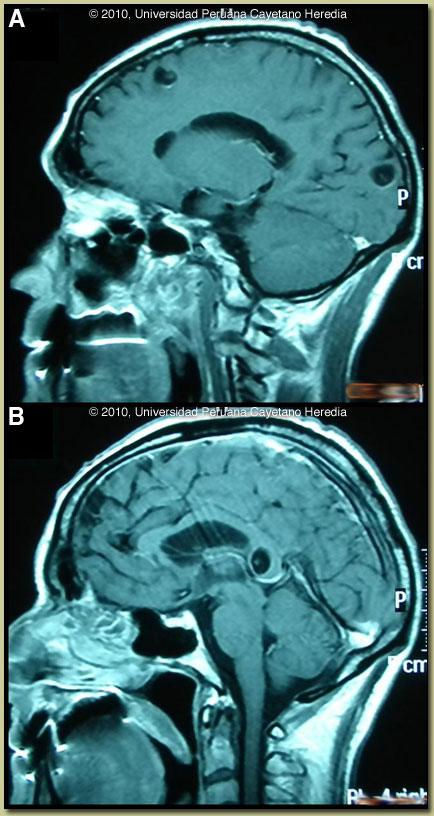

Discussion: The MRIs shown in Images A & B are diagnostic without any further testing; visualization of a fluid filled cyst with a scolex inside [arrow, Image A] is diagnostic. The scolex is the head of the larval T. solium tapeworm. Edema around a dying cyst is often the trigger for onset of seizures in infected individuals. In this case a Western blot was performed and was positive. Fortunately, no intraventricular lesions or signs of intracranial hypertension were seen in this patient, as such cysts are more difficult to manage.

Cysticercosis is infection with the larval stages of the human pork tapeworm Taenia solium. Humans acquire cysticercosis after ingesting eggs of T. solium in material contaminated with feces originating in human tapeworm carriers. Humans that do not eat pork can get cysticercosis. Ingestion of contaminated pork results in humans getting an adult intestinal tapeworm, not cysticercosis. Cysticercosis is common in many developing countries and very common in rural agricultural areas of Perú. In developed countries the long-lived cysticerci are increasingly seen as immigration from affected areas rises. Occasional transmission by tapeworm carriers to those who have never left non-endemic countries is reported. Ingested T. solium eggs hatch in the stomach and are then carried to the muscles and other tissues where the larvae encyst and reach their usual size of about 1 cm within a few months. Clinical manifestations depend on the affected organ but neurocysticercosis causes the most morbidity. The cysticerci seem able to evade the immune system and are thought to remain viable for several years without causing any inflammatory response. Most clinical symptoms are the direct result of inflammatory responses that accompany the eventual cyst degeneration. Epileptic seizures are the primary or sole clinical manifestation in up to 80% of patients. In endemic regions, new onset seizures in teenagers or young adults are most likely due to neurocysticercosis. Cysticerci can also cause symptoms because of mass effect, impingement on a vital structure, or blockage of CSF circulation especially if the cyst is intraventricular. In all cysticercosis patients, seizures need to be managed as per any other form of epilepsy. Treatment of parenchymal neurocysticercosis with antiparasitic drugs such as albendazole is increasingly accepted even when there are few lesions. Albendazole clearly kills the cysts, but may lead to added inflammation and exacerbation of symptoms, which is usually dealt with by empiric concomitant use of steroids. Therapeutic decisions should be based on the number, location, and viability of the cysts. Patients in whom all lesions are already calcified should receive no anti-parasitic treatment. Recent work indicates that long-standing calcified lesions can sometimes provoke peri-lesional edema, which may need treatment with steroids as well as anti-seizure medication. Intraventricular shunting may be necessary if intracranial hypertension results from treatment. Neurocysticercosis is a variable disease and treatment approaches need to be individualized to a large number of differing clinical presentations [Neurology. 2006 Oct 10;67(7):1120-7]. Our patient was treated with albendazole 15mg/kg/d for one-month plus prednisone 1mg/kg/d tapering the dose progressively for a total duration of one month, and phenytoin. After discussion with Gorgas Course professor and consultant Hector Hugo-García, the duration of treatment beyond the standard 8 days was undertaken, based on the proximity of one lesion to the 3rd ventricle [Image B]. He tolerated the therapy but his headache failed to resolve. Repeat MRI 5 months later [Images C & D] showed good involution of the peri-ventricular lesion but little effect of treatment on the parenchymal lesions. A further course of treatment was decided after follow-up consultation with Dr García. His experience is that a significant resolution in the size of many lesions should have occurred in the 5-month follow-up period. Not achieving that is an indication for longer duration of treatment and perhaps for combination therapy. Our patient was started on a combination of albendazol 15mg/kg/d plus praziquantel 50mg/kg/d and steroids, with plan to give these drugs for at least one month; this regimen is currently being evaluated in a phase II clinical trial compared with albendazole.